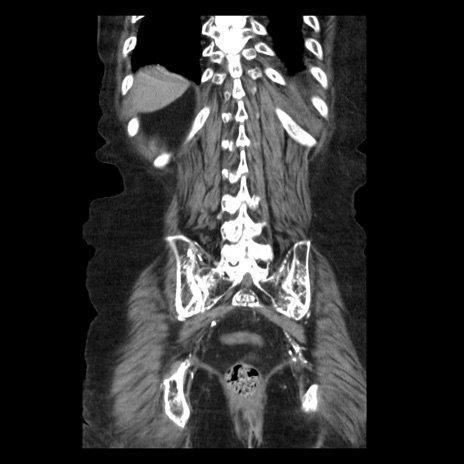

症例14(冠状断像)

【症例】 90歳代女性

【主訴】 腹痛・嘔吐

【現病歴】今朝から左側腹部痛を認めた。 経過観察していたが、嘔吐を認めたため来院。

【既往歴】 子宮癌術後

【身体所見】 意識清明、BP 127/54mmHg、P 98bpm Sp02 95%(RA)、BT 35.8°C、腹部平坦・軟腸ぜん動音聴取良好、右下腹部圧痛(+) 反跳痛なし

【データ】WBC 9800、CRP 0.46